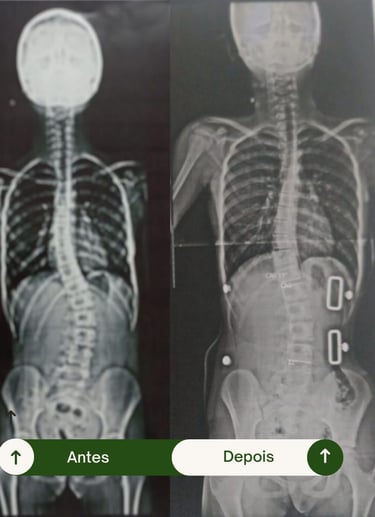

Resultados Comprovados

Transformando vidas por meio da fisioterapia e da tecnologia 3D.

Veja como nossos pacientes reconquistaram mobilidade, conforto e confiança.